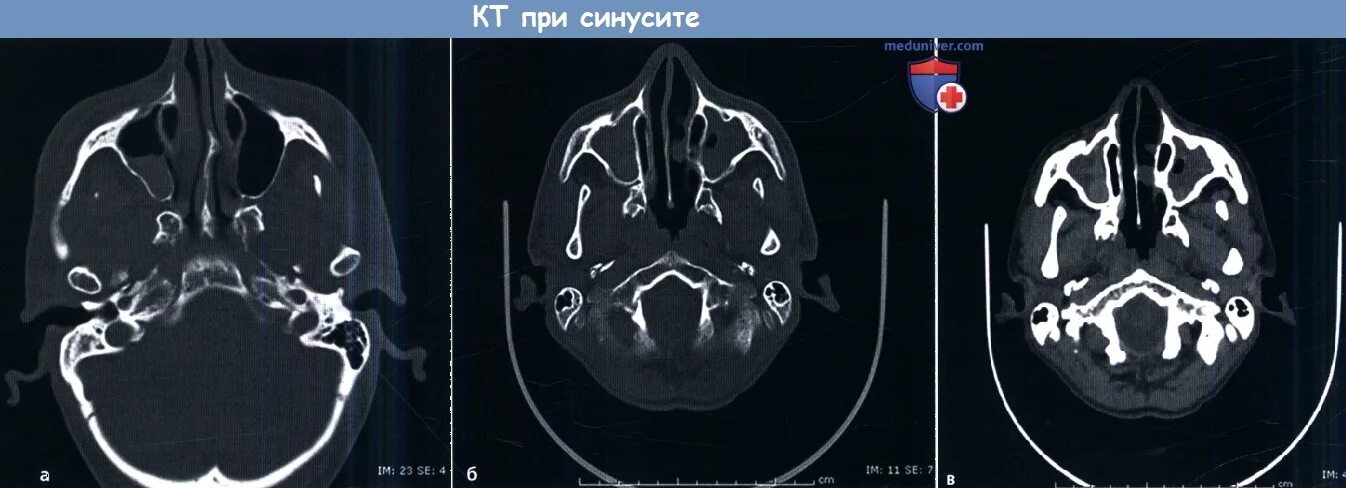

Синусит на кт